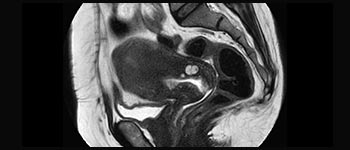

Pelvis

Información general sobre la pelvis femenina